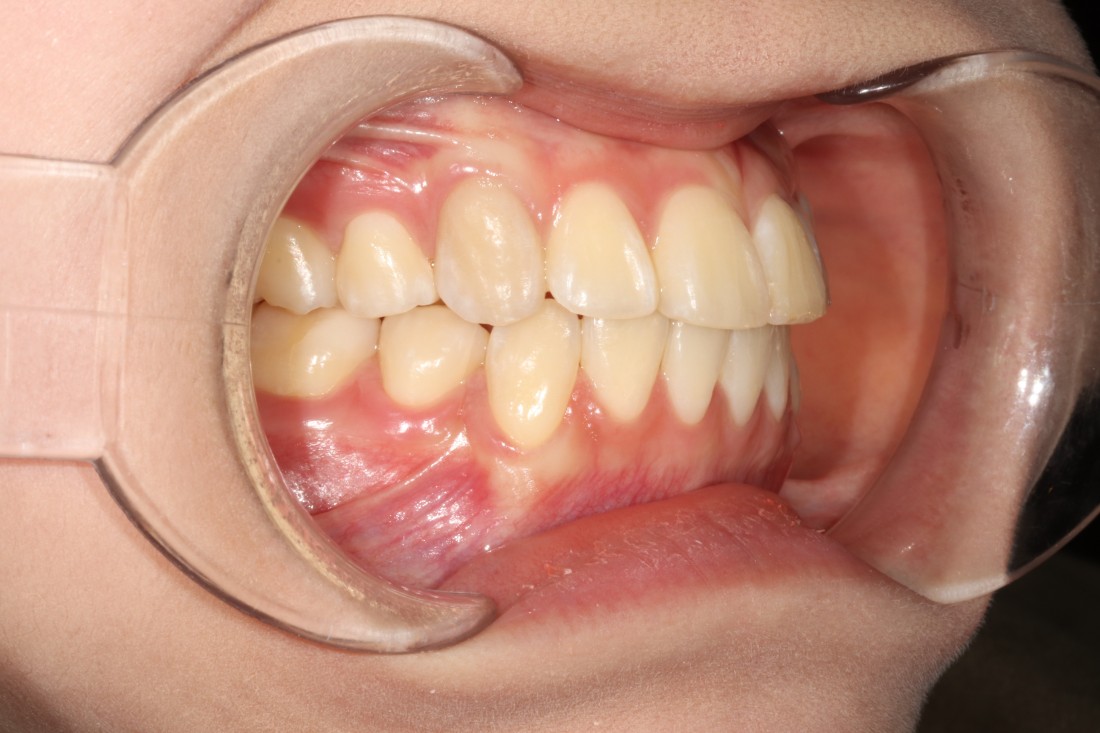

수완동 교정치과 중에서

임플란트와 치아교정 진료를

동시에 진행하여

최고의 치료효율을 낼 수 있는 치과는

서울우리아이치과 입니다.

교정전문의 한 명만 있는 것이 아닌,

분과별 전문의 진료를

함께 하고 있기 때문에

치아교정 + 임플란트

치아교정 + 라미네이트

치아교정 + 턱관절질환

다양한 전문의 조합으로

최상의 치료효율을 낼 수 있습니다.

![]() | ![]() |

전문의 5인 대표원장의 협진 시스템으로

교정과전문의 치아교정과

구강외과전문의 임플란트를

동시에 진료하기 때문에

적절한 시기에 최상의 치료효과로

교정기간은 단축하고,

성공적인 임플란트 식립까지

가능한 수완동 교정치과입니다.